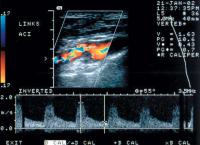

Duplexsonographie - Karotis

Abbildung 6: Hämodymisch nicht wirksame, eher fibröse, nicht glatte Plaques in ACI links (Vmax 0,7/0,2 m/sec)

Keywords: Arteria carotis internaDuplexsonographiePlaque